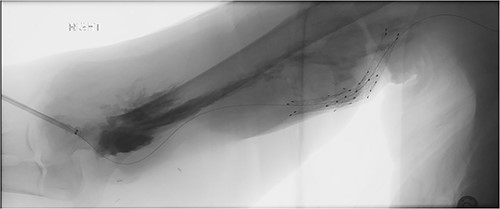

A 78-year-old female with history of coronary artery disease, hypertension, hyperlipidemia, and end-stage renal disease on hemodialysis through a right brachio-basilic arteriovenous fistula presented to the hospital with prolonged bleeding after dialysis. She was not taking any antiplatelet or anticoagulation medication. She had previously undergone stenting of the proximal basilic vein due to venous stenosis. Right upper extremity fistulogram identified recurrent basilic vein stenosis within the previous stents. Balloon venoplasty was performed via 6 Fr sheath. Repeat fistulogram demonstrated persistent stenosis of the proximal basilic vein and so the sheath was upsized for Viabahn stent placement. During the sheath exchange, there was some contrast extravasation around the sheath access site (Fig. 1), which resolved with a longer 7 Fr sheath. Completion fistulogram did not show residual stenosis and the patient was discharged the following day. The patient continued to use her fistula for hemodialysis during the next 2 months.

Fistulogram demonstrating contrast extravasation around the sheath access site.